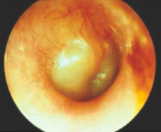

acute otitis media (AOM)

acute otitis media

rapid onset, with signs/sx of inflammation of ME, most often with otalgia and bulging TM

acute OM